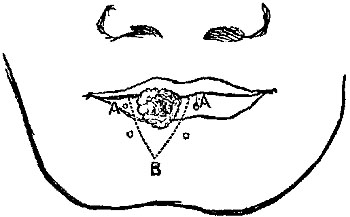

The four plates which precede the letterpress were drawn on wood (from original photographs) by Mr. D.W. Williamson, Melbourne Place, and the lines of incision for the various operations were added by the author.

The rough woodcuts scattered through the work were drawn on wood by the author, and for their roughness he, not his engraver, is responsible. He also hopes that the references in the letterpress will be accepted as sufficient acknowledgment of the true ownership, in those few instances in which the idea of the diagram has been borrowed.